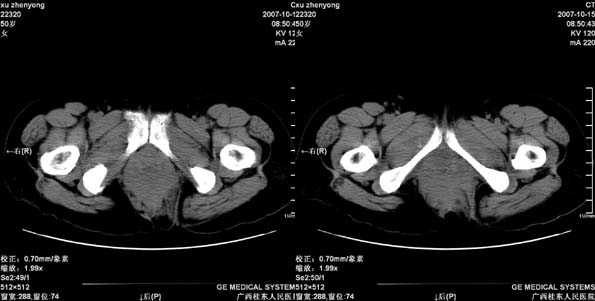

患者,女 50岁.会阴部坠胀感一月余,有痔疮病史,近期有便血;患者今年5月分结肠镜检查未见异常(由于患者不愿意ct增强扫描)没做增强,现准备手术,请各位老师会诊.

直肠壁明显增厚,呈块状表现,肠腔狭窄闭塞,考虑ca

直肠壁增厚明显,周围脂肪间隙模糊,见有小淋巴结显示,前方与阴道后壁分解不清。考虑直肠癌可能性大

偏侧直肠壁增厚,支持直肠癌,不除外内痔.

不做强化,但平扫保留灌肠一定要做好。现在看直肠壁增厚明显,周围脂肪间隙模糊,前方与阴道后壁分界不清。考虑直肠癌可能性大

直肠下端及肛门周围可见软组织改变,如果5月份检查的结肠镜结果可靠,那么本病例痔的可能性还是很大的。肿瘤生长的不会如此之快。